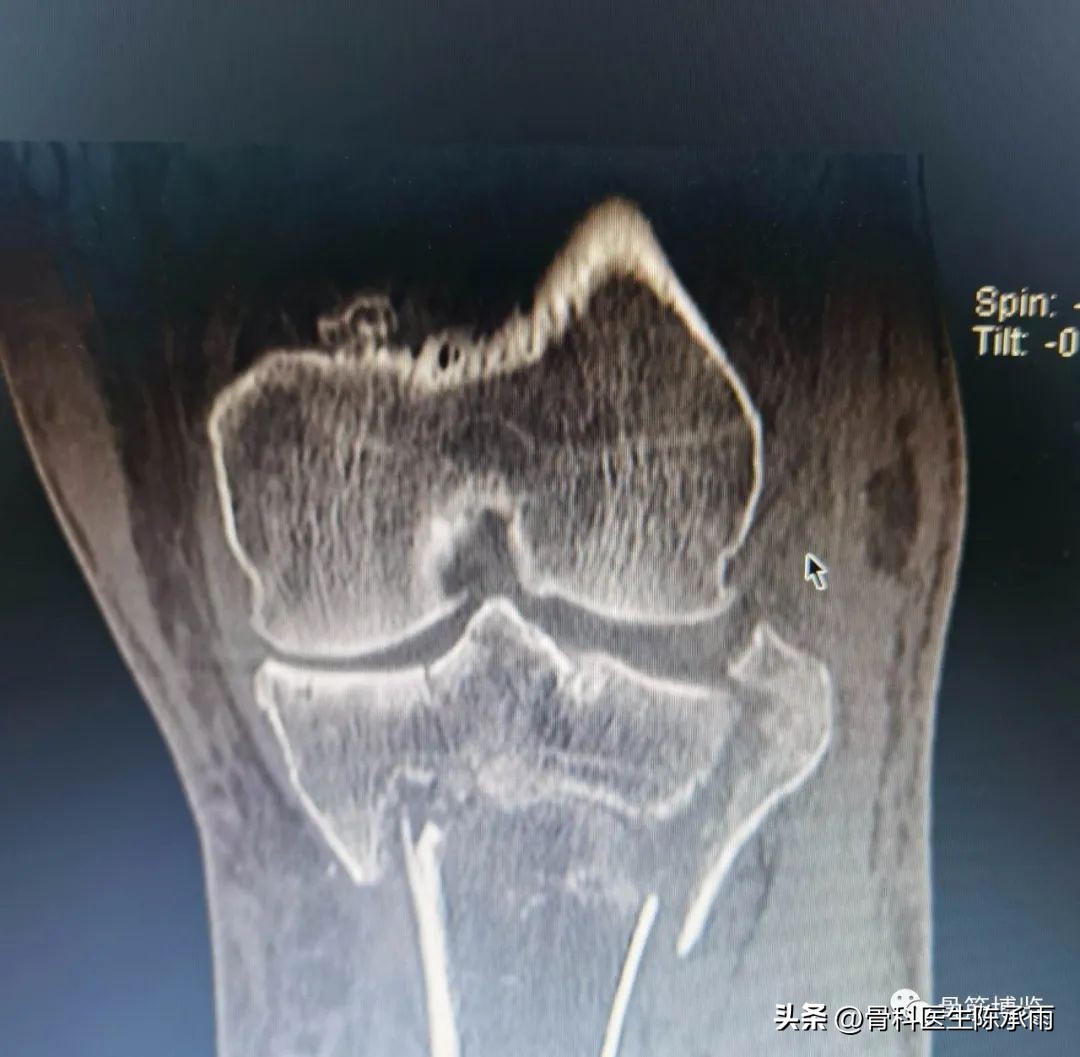

近段时间的胫骨平台骨折,没来得及详细整理

胫骨平台骨折的分型比较多,我们临床上常用的就是Schatzker分型和AO骨折的分型,还有骨折脱位的Hohi-Moore分型,这是我们常用的三个分型。